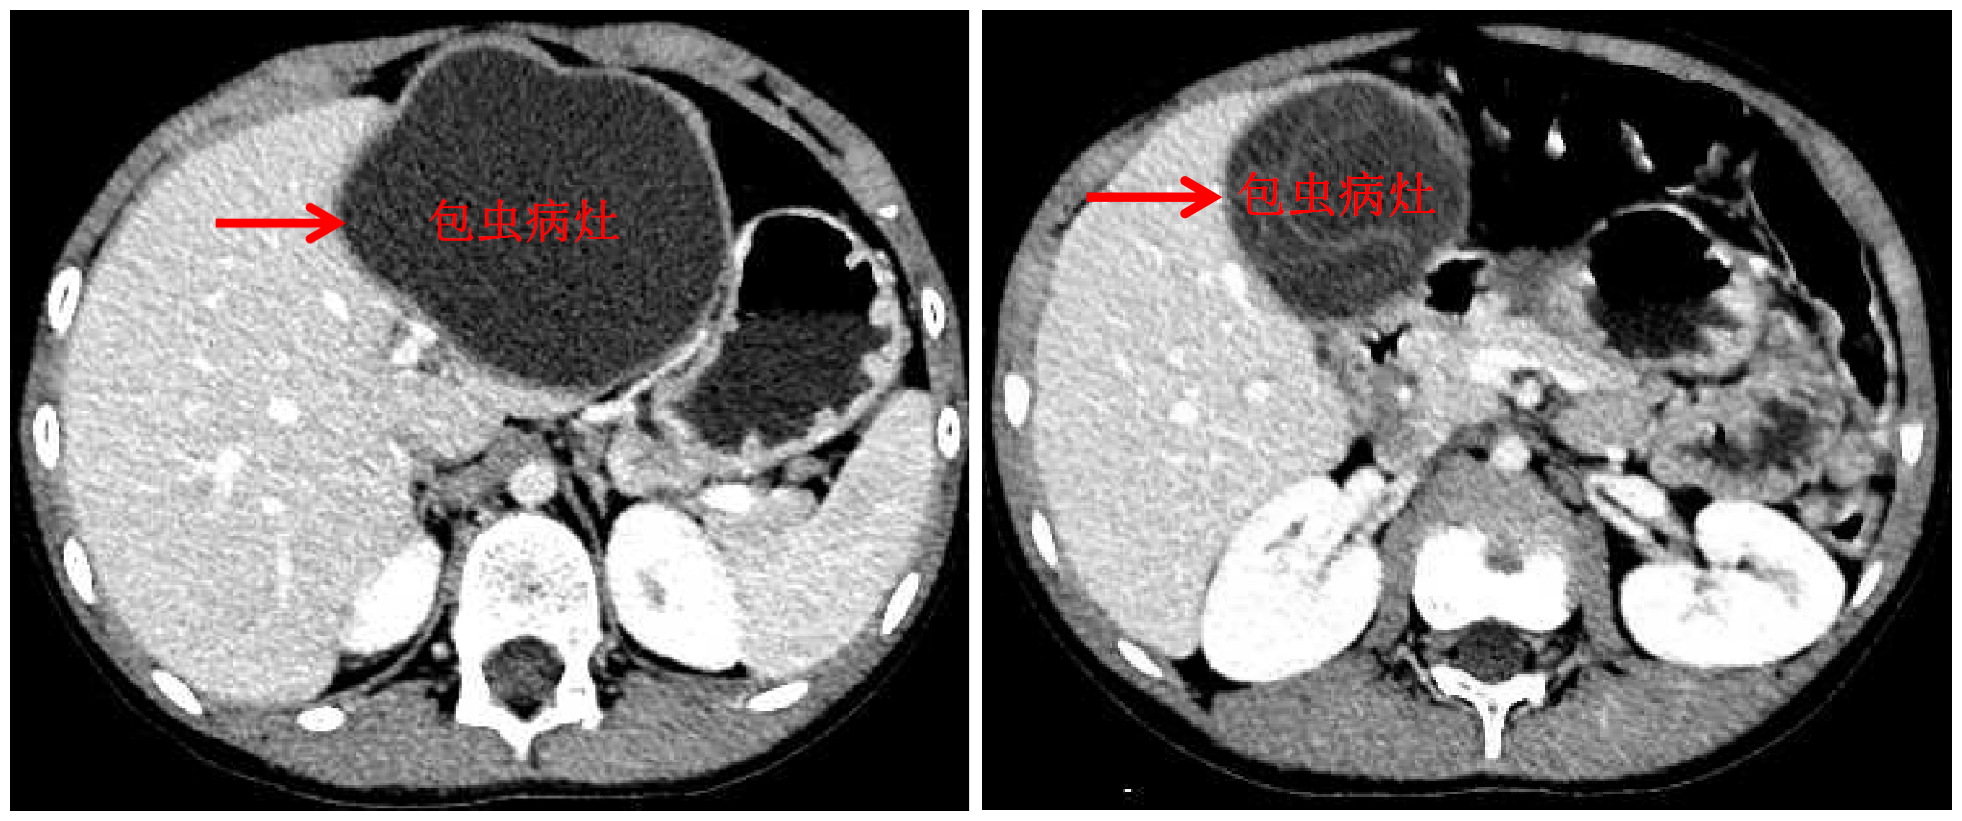

清华新闻网10月13日电 国庆前,8岁的小扎西被父亲带到了西藏大学附属拉萨市人民医院普外科,此次距离孩子确诊肝包虫病已有一年之久。腹部影像显示,小扎西体内的囊型肝包虫病已经侵袭了左肝大部。

面对肝包虫病患儿,beat365英国官方网站附属北京清华长庚医院肝胆胰外科援藏医生、现任拉萨市人民医院普外科主任王学栋已经历过丰富的历练——由董家鸿院士带领的清华长庚肝胆胰团队常年深入青海、四川等游牧地区义诊,为终末期肝包虫病患者提供治疗。但对于小扎西,无疑开腹摘除术是更加简单、安全的方法,而腹腔镜下切除病灶,能达成藏族同胞对微创的要求,却是困难重重——病灶巨大,腔镜下解剖及显露肝门困难,且病灶紧贴肝中静脉,保留肝中静脉较困难。

包虫病灶